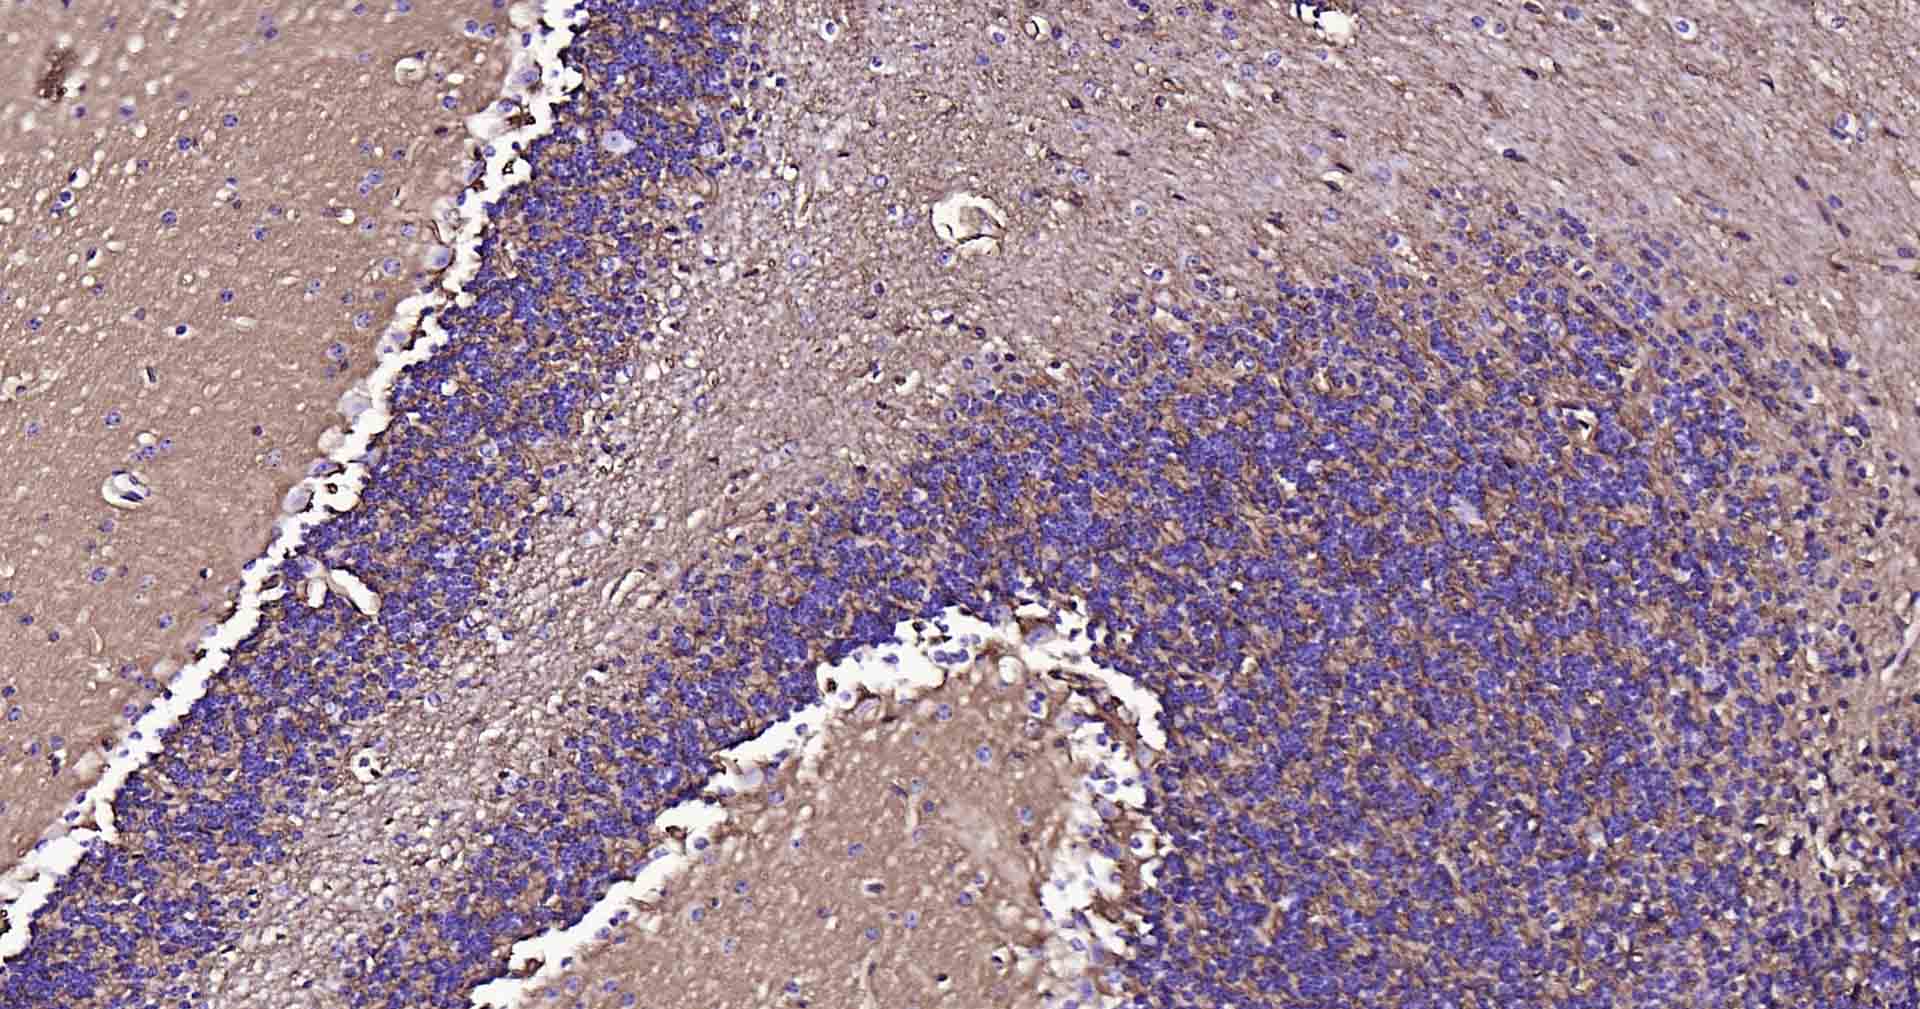

Paraformaldehyde-fixed, paraffin embedded Human Cerebellum; Antigen retrieval by boiling in sodium citrate buffer (pH6.0) for 15 min; Antibody incubation with AQP4 Monoclonal Antibody, Unconjugated(bsm-61035R) at 1:100 overnight at 4°C, followed by conjugation to the SP Kit (Rabbit, SP-0023) and DAB (C-0010) staining.

Paraformaldehyde-fixed, paraffin embedded Rat Cerebellum; Antigen retrieval by boiling in sodium citrate buffer (pH6.0) for 15 min; Antibody incubation with AQP4 Monoclonal Antibody, Unconjugated(bsm-61035R) at 1:100 overnight at 4°C, followed by conjugation to the SP Kit (Rabbit, SP-0023) and DAB (C-0010) staining.

Paraformaldehyde-fixed, paraffin embedded Mouse Cerebellum; Antigen retrieval by boiling in sodium citrate buffer (pH6.0) for 15 min; Antibody incubation with AQP4 Monoclonal Antibody, Unconjugated(bsm-61035R) at 1:100 overnight at 4°C, followed by conjugation to the SP Kit (Rabbit, SP-0023) and DAB (C-0010) staining.